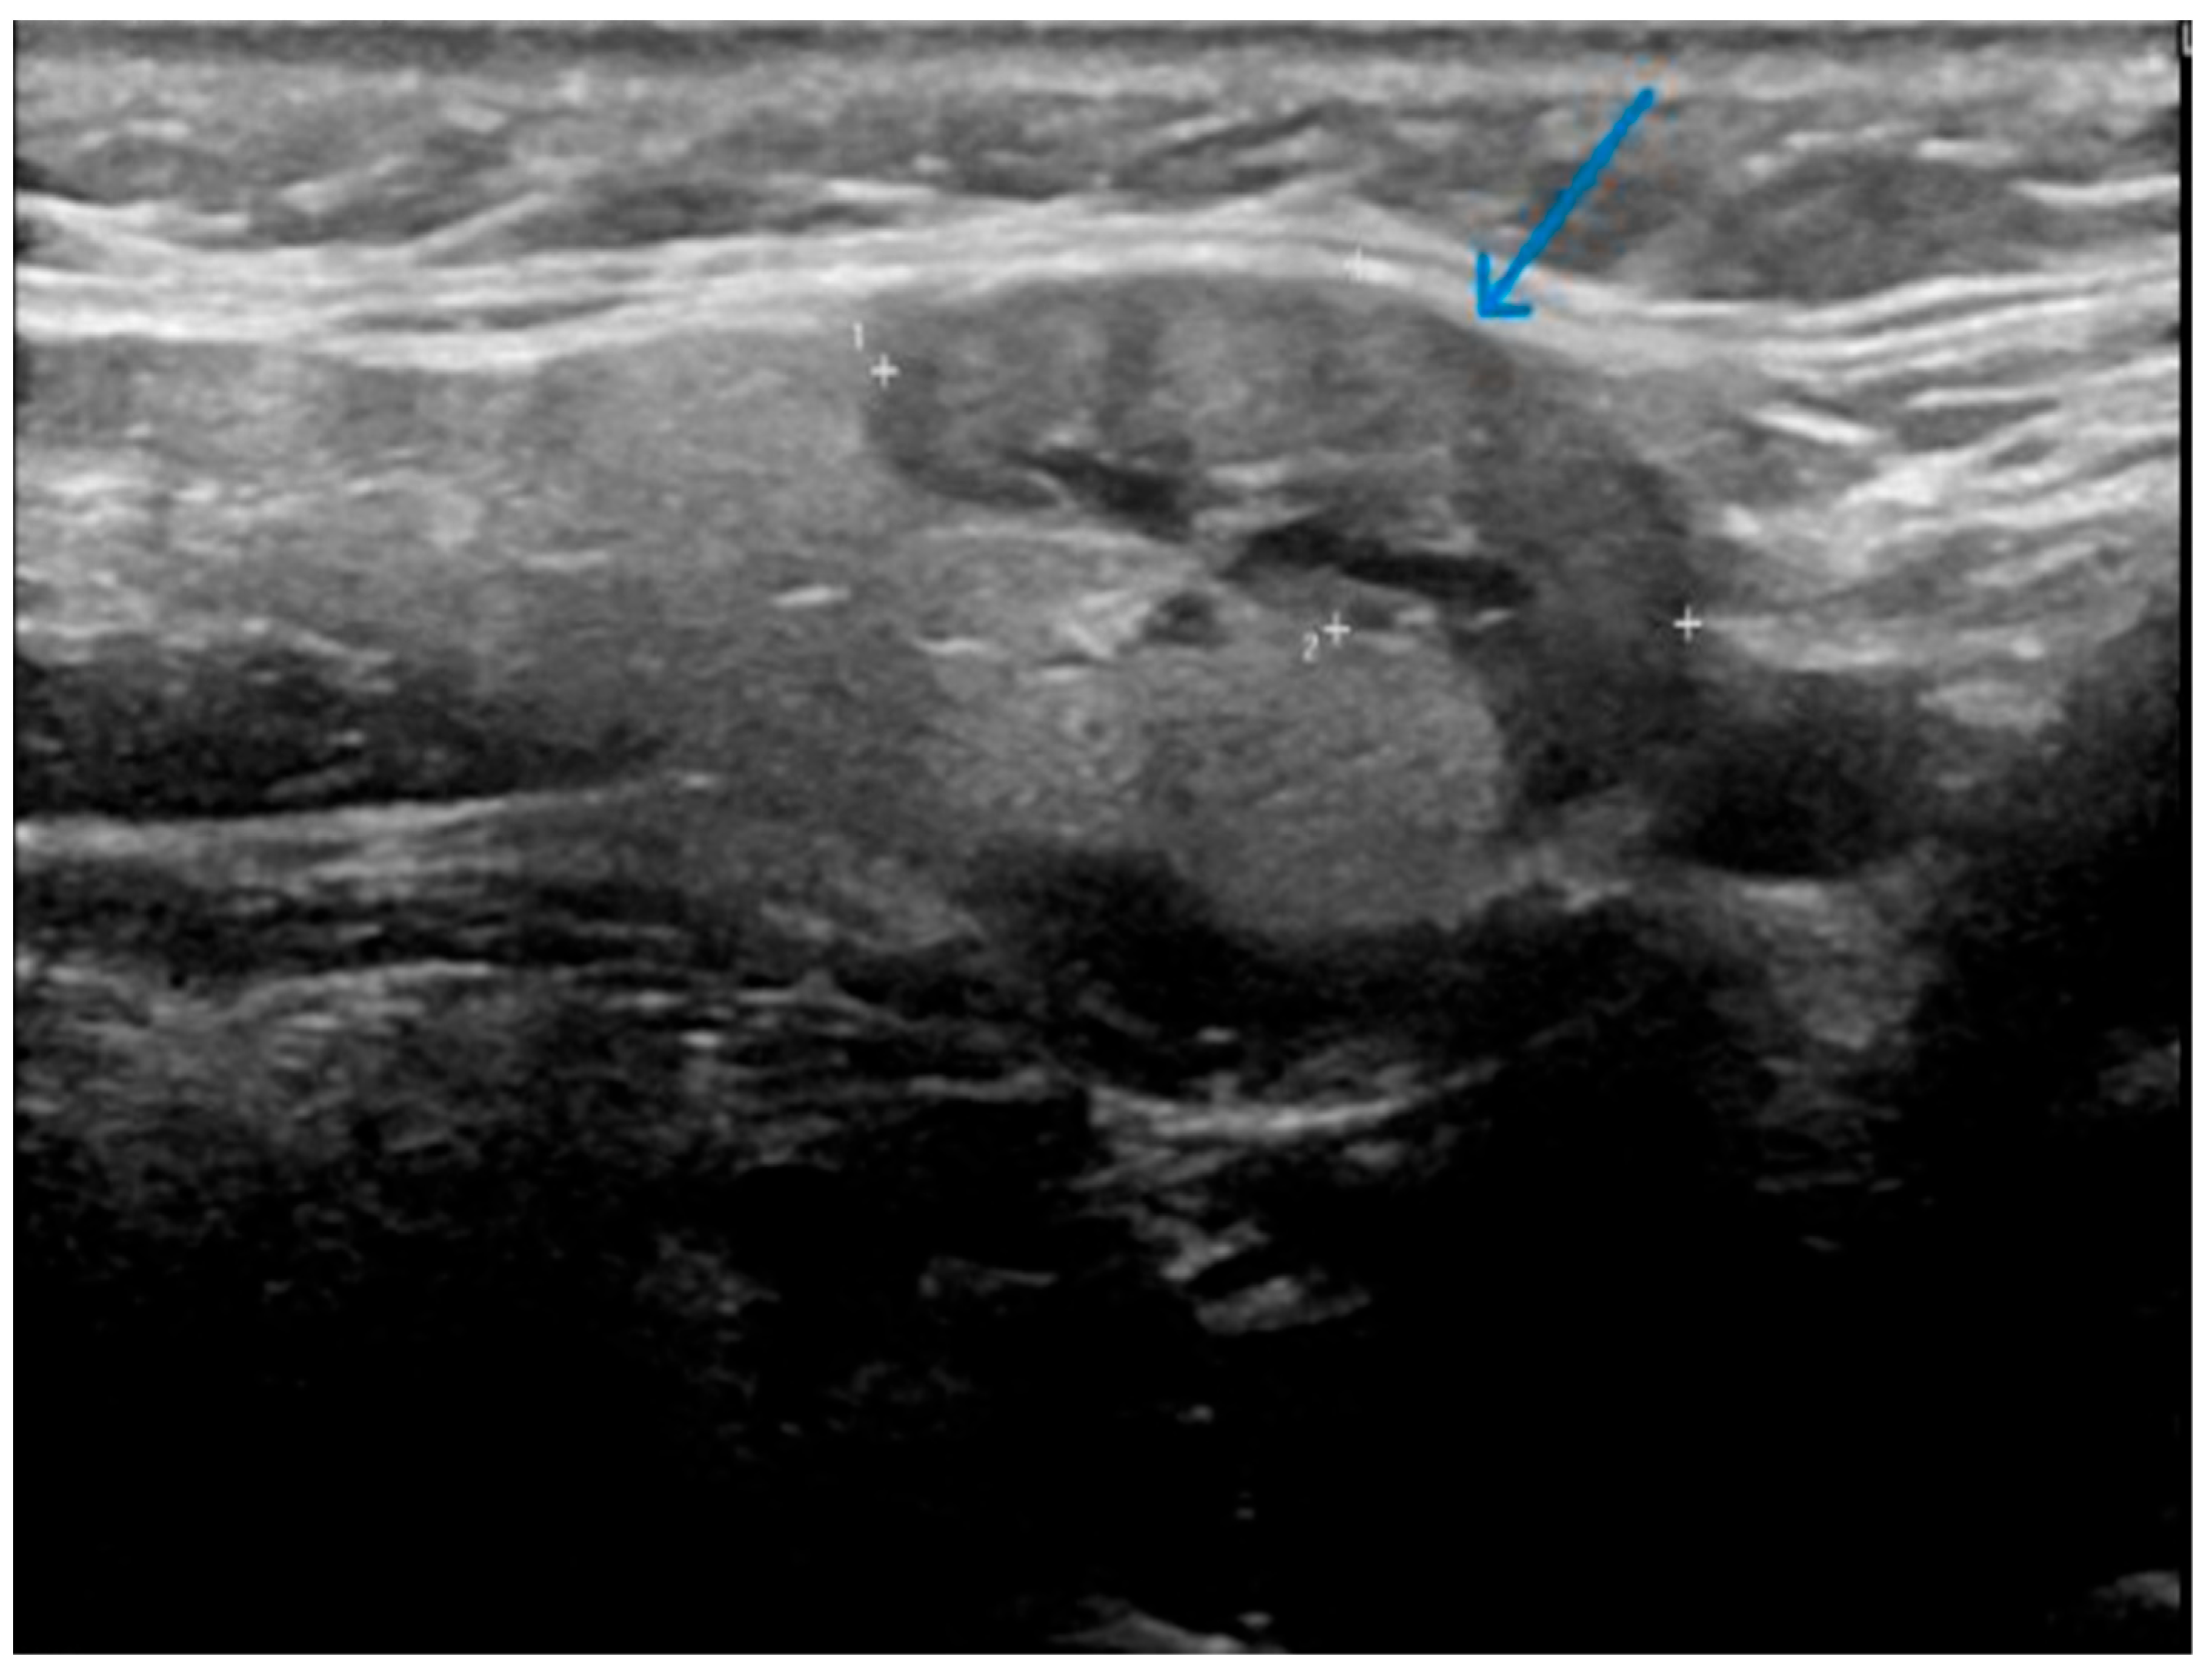

- Well-demarcated geographical area of low echogenicity with increased vascularity;

- Mild focal intrinsic duct dilatation within the SMG;

- No suggestion of a neoplasm or space-occupying lesion.